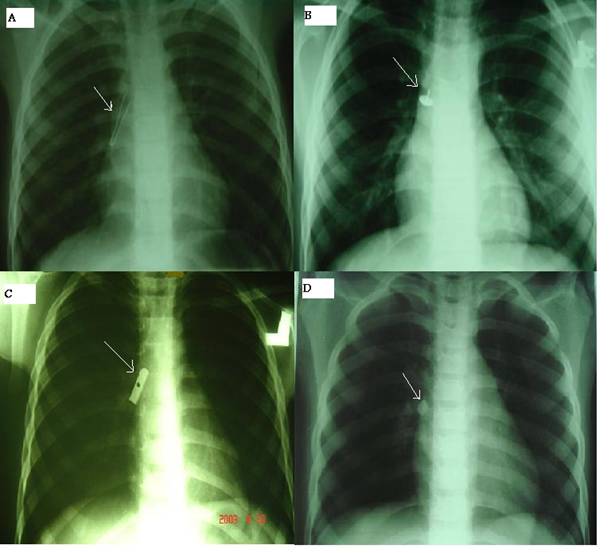

The duration of enlodgment of foreign body ranged from 0 hours to more than 6 month (Table 2). In fifty seven patients recovery was un-eventful except mild laryngeal edema which was treated by steroids and humidified air. We had mortality in two patients due to brain anoxia. Sixty patients had multiple FBs in both right and left bronchus. Mostly patients were discharged from hospital on third day. Seven hundred-forty one patients (73.03%) presented with cough, 134 patients (13.18%) had cyanosis and 47 patients (4.64 %) had dyspnea as shown in table 3. Rare cases (Figure) were removed by appropriate tools and techniques under bronchoscopy. A cylinder-shaped plastic whistle removed from the main right bronchus by a grasper forceps (Figure 1A), a thumbtack was removed by using a crocodile forceps (Figure 1B), a sharpener was removed by a cup forceps (Figure 1C), and the dental piece FB was extracted (Figure 1D).

Figure 1

Different foreign bodies removed by bronchoscopy (arrows). (A) Endoscopic image of a whistle lodged in the right bronchus. (B) A thumbtack removed from a patient with bronchoscopy. (C) Endoscopic image 8 of a sharpener in the right middle lobe bronchus. (D) A dental piece removed from a patient.